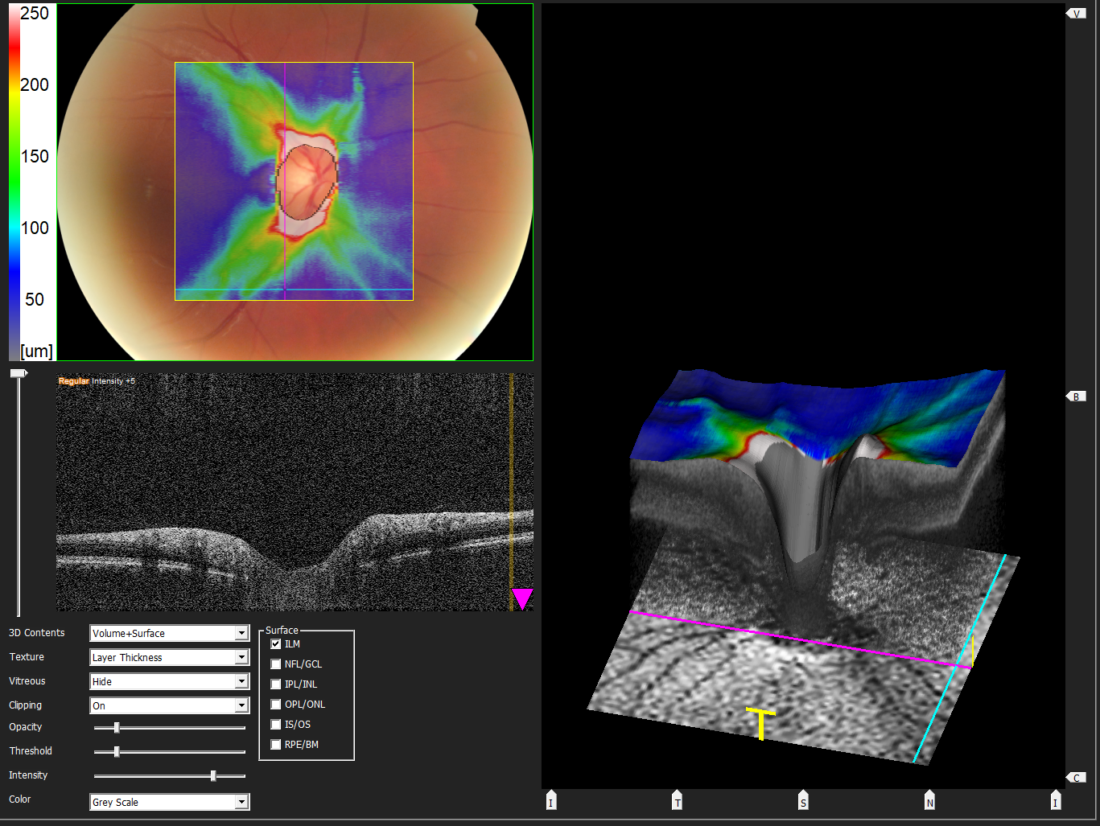

Der Augendruck alleine sagt nicht viel aus. Er muss im Zusammenhang mit der Gesamtsituation des Auges beurteilt werden, insbesondere mit der Erscheinung des Sehnerven (Netzhaut) und der Anatomie der vorderen Augenkammer.

Die Augen Vorsorge Untersuchung heisst bei uns „Panorama Check“, weil unter anderem mit einer Ultra-Weitwinkel Kamera die Netzhaut abgebildet wird. Dazu wird das Auge sorgfältig von vorne bis hinten angeschaut. Besonderer Fokus wird gelegt auf die Netzhaut mit dem Sehnerv und der Makula, aber auch die Augenlinse, die Vorderkammer, die für die Regulierung des Augendruckes wichtig ist. In der heutigen Zeit mit intensiver Bildschirmnutzung wird aber auch der Tränenfilm, die Schleimhaut und die Hornhaut kurz angeschaut. Zudem erfolgen Funktionsteste, um gröbere Auffälligkeiten in der Augenbeweglichkeit oder Pupillenreaktion festzustellen.

Der Augendruck selbst wurde früher als sehr wichtig angeschaut. Er dient zwar auch heute noch als Faktor in der Erkennung, Diagnose und Behandlung eines Glaukoms (eines grünen Stars). Das Verständnis der Krankheit Glaukom hat sich aber grundlegend geändert, da viele Betroffene ein sogenanntes Normaldruckglaukom haben, während andere resilient sind und trotz zu hohem Druck nie einen degenerativen Schaden entwickeln.

Der Augendruck ist also nur eines der Puzzleteile. Nachfolgend sehen Sie Aufnahmen wie sie bei uns im Rahmen eines „Panorama Check“ entstehen.